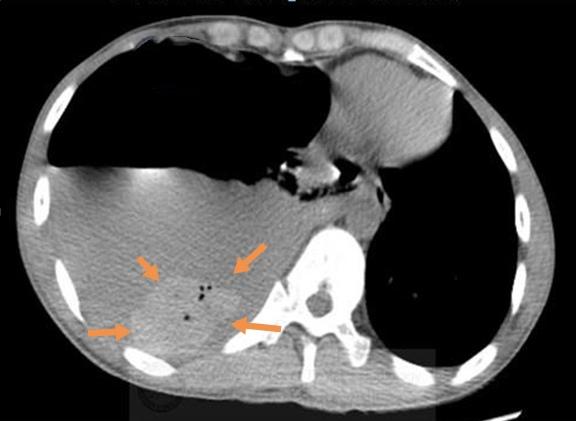

胸部CT显示右侧液气胸,胸腔积液和气体压迫肺策划,导致呼吸困难和不能深吸气,并且挤压心脏向左侧移位。

再看纵隔窗:

在大量灰色的胸水里,有一块椭圆形的小团块沉在水底,里面还有4个小气泡。

这个病人不是单纯的液气胸,准确点说,他是自发性血气胸,出血量在400ml以上了。

增强扫描发现右肺尖背侧造影剂渗漏,符合活动性出血,需要手术!